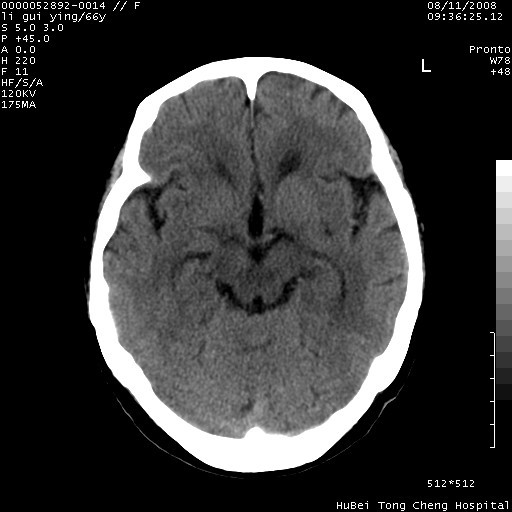

以下是引用yangyudong333在2008-8-12 12:22:00的发言:[br]1.病灶呈圆形[br]2.周围无水肿带[br]3.密度不均匀,内有点状钙化[br]4.无占位效应[br] 考虑良性占位性病变,血管瘤可能性大